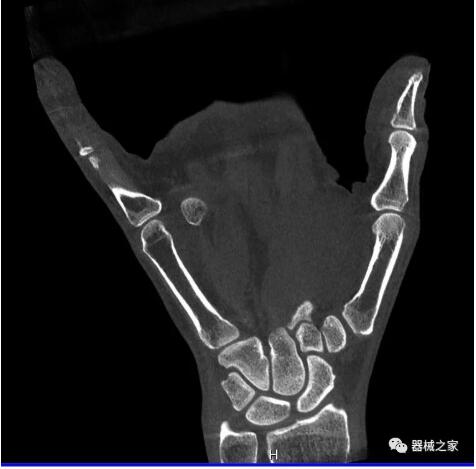

另外一款被稱為世界上最小的CT,它的重量僅300磅,不僅能夠掃查足部,還可以檢查膝蓋和上肢等。

這款CT使用非常方便,通過上下移動保持與患者的手臂或者雙腿齊平,掃描快速,僅需要30秒左右就可以完成掃查。

以下是這些“特立獨行”的CT所拍出來的圖像: